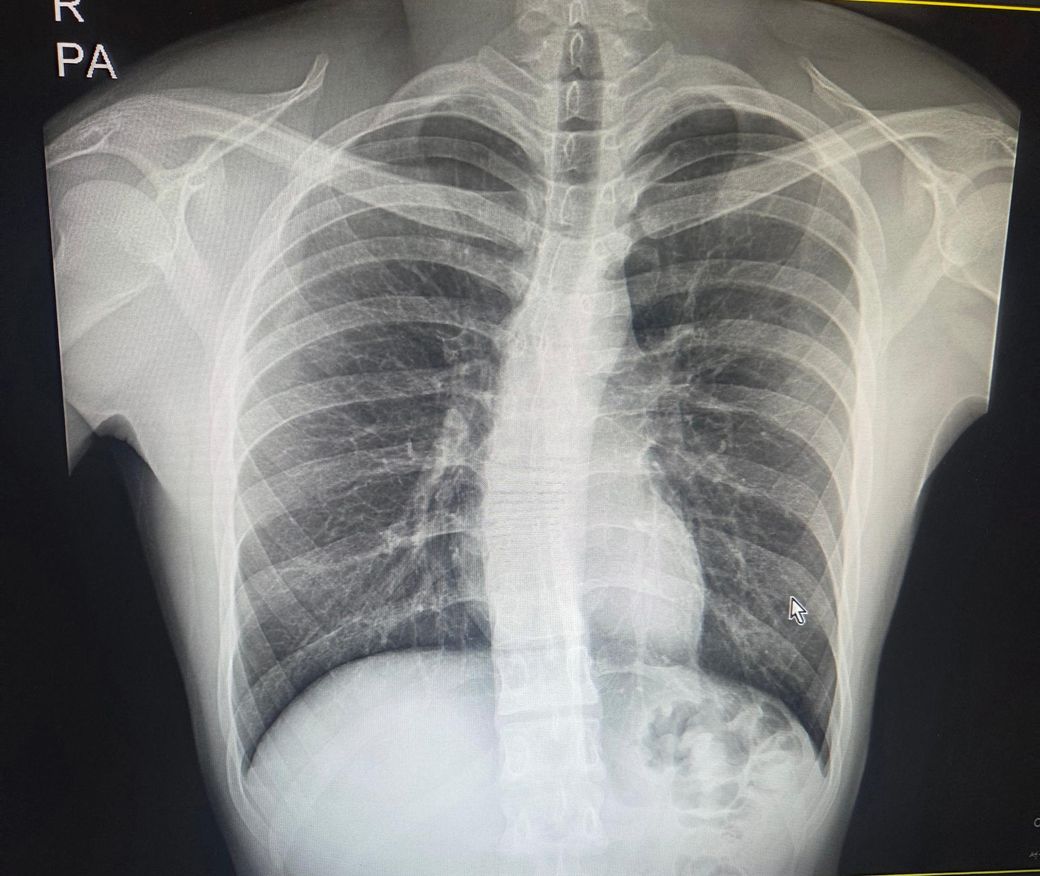

사진 한장만으로 정확한 각도를 재는건 한계가 있지만, 지금 보이는 척추는 흉추쪽이 살짝 휘어있는 측만이 의심됩니다. 다만 갈비뼈 비대친이 심하게 보이는 정도는 아니라서 심한측만으로 보이진 않습니다. 일반적으로 육안상 심하다는 느낌이 드는 경우는 보통30도 이상인 경우가 많고, 이 사진은 그정도로 크게 휘어보이진 않습니다. 21살이면 성장판이 거의 닫혀서 청소년기처럼 각도가 빠르게 악화되는 경우는 상대적으로 낮습니다. 자세 불균형을 잡고 통증을 줄이며 악화를 막는 목적으로 교정운동을 하니 꼭 추천드립니다.

각도는 프로그램을 이용하여 정확히 측정해보아야 하겠지만, 매우 심각한 상태의 측만증이라고 보기에는 휘어진 각도가 두드러지거나 큰 상태는 아닙니다.

현재로썬 사진만으론 판단하긴 어렵지만 심한 척추측만증보단 경도 또는 중증으로 보여집니다.

X-ray 한 장만으로 정확한 각도(Cobb 각)는 측정이 어럽지만,

심한 편으로 보이진 않고 경도~중등도 가능성이 있어 보입니다.

육안상 추정으로는 10~25도 전후 범위가 의심되며, 정확한 평가가는 정형외과 측정이 필요합니다.

척추 측만증의 경우 콥 각도를 이용하여 측정하게 되는데 콥 각도가 10도 이상일 경우 척추 측만증으로 진단하게 됩니다. 현재 사진으로 정확한 각도는 알기 어렵지만 심한 측만증은 아니므로 척추 보조기 등을 착용하여 치료를 고려해 볼 수 있습니다. 정형외과 내원하여 이에 대한 진료를 보시는 것을 권해드립니다.